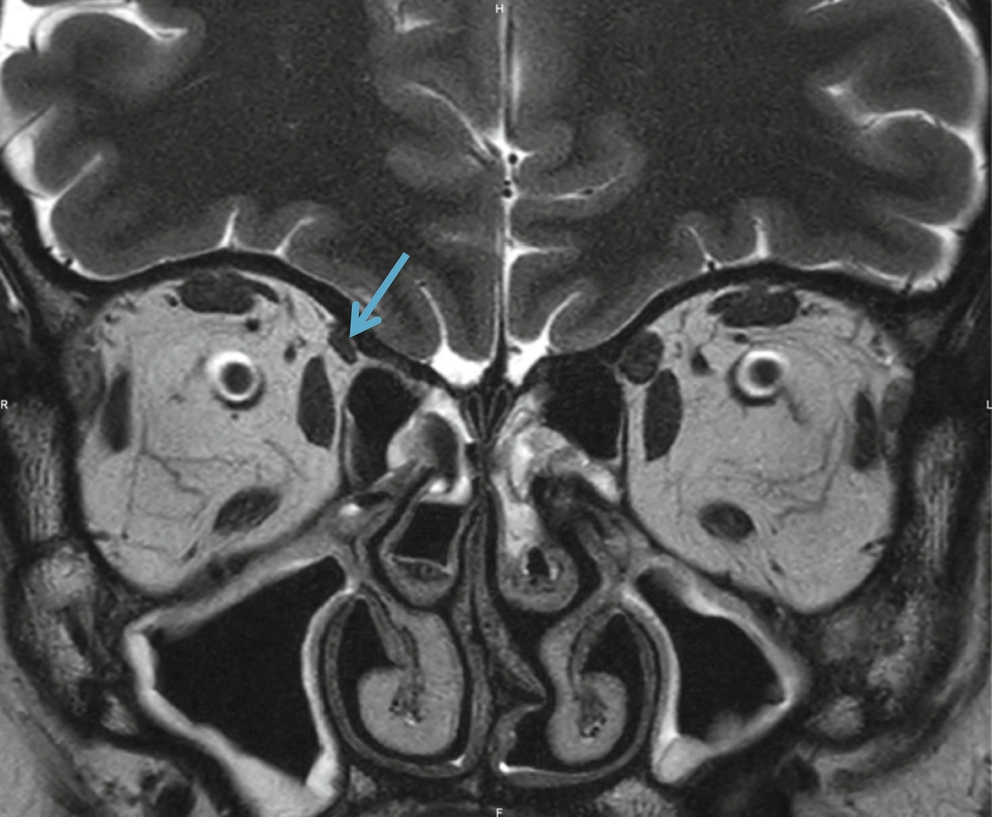

Cas particulier   : le bilan d'une possible HIC idiopathique est celui d'une recherche de thrombose veineuse auquel on ajoute des coupes coronales T2 fines centrées sur les voies optiques antérieures à la recherche d'un élargissement des espaces périoptiques, de signes de souffrance (hypersignal T2 des nerfs) et d'une arachnoïdocèle intrasellaire (fig. 2-52

Fig. 2-52

Hypertension intracrânienne idiopathique en T2 (a, c, d) et T2 FAT-SAT(b).Dilatation des espaces périoptiques (flèches bleues) et autour des III (flèche verte). Arachnoïdocèle intrasellaire (flèche rouge). Évolution visuelle défavorable avec apparition d'un hypersignal T2 des nerfs optique (flèches jaunes).

). L'ARM veineuse montre des sténoses bilatérales des sinus latéraux (voir fig. 2-31) [23,24].